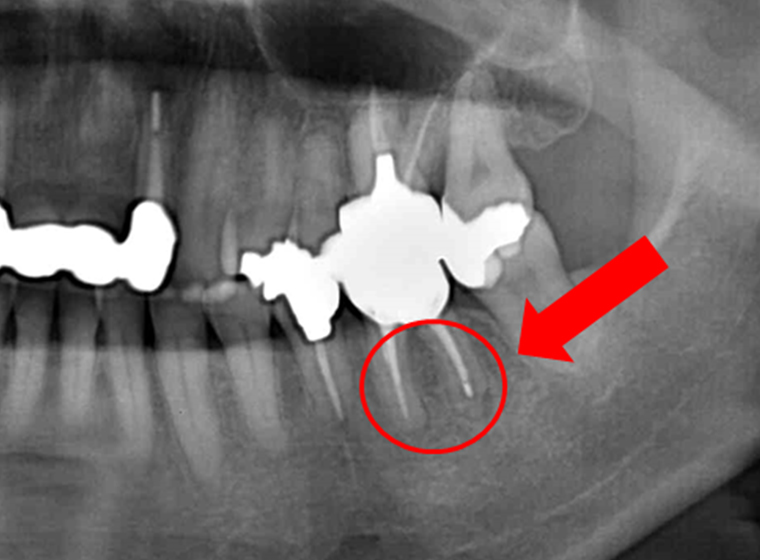

前歯の症例

左の術前写真は根の先が黒い影で覆われています。根尖病巣で膿のかたまりが顎の骨を溶かしているのです。右の術後1年の写真は黒い影がなくなり、顎の骨が復活しています。通常では抜歯が選択される症例ですが、当院では歯を残すことを優先します。